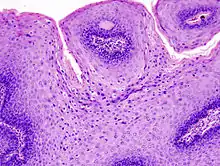

Micrograph of a genital wart with the characteristic changes (parakeratosis, koilocytes, papillomatosis). H&E stain.

The diagnosis of genital warts is most often made visually, but may require confirmation by biopsy in some cases.[19] Smaller warts may occasionally be confused with molluscum contagiosum.[18] Genital warts, histopathologically, characteristically rise above the skin surface due to enlargement of the dermal papillae, have parakeratosis and the characteristic nuclear changes typical of HPV infections (nuclear enlargement with perinuclear clearing). DNA tests are available for diagnosis of high-risk HPV infections. Because genital warts are caused by low-risk HPV types, DNA tests cannot be used for diagnosis of genital warts or other low-risk HPV infections.[4]